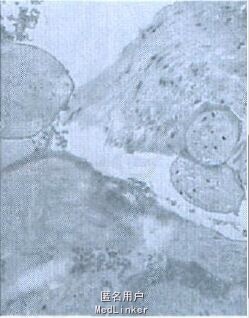

予以行诊刮术,术后病理:(宫内)送检物大部分为血凝块, 其内可见坏死变性的胎盘绒毛组织(图4);病理诊断:稽留流产。